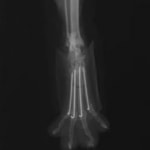

症例3:キルシュナーワイヤーのピンニングによる整復

ペルシャ猫 11ヶ月齢 雄

他院にて左大腿骨遠位の成長板骨折(salter-harrisⅠ型)が認められており、治療相談を目的として来院。当院にて、キルシュナーワイヤーを用いたピンニングにより骨折部位の整復を行いました。術後の経過は良好で、現在も経過観察中です。

術前レントゲン

術後レントゲン

機器

Arthrex社のターゲティングデバイスを用いてピンニングの位置を調整することで、確実な固定を行っています。当院ではこの手術器具以外にも、人の手術にも使用される様々な器具を導入し、手術精度を高め、また医療メーカーと新しい器具の開発、試作にも取り組んでおります。